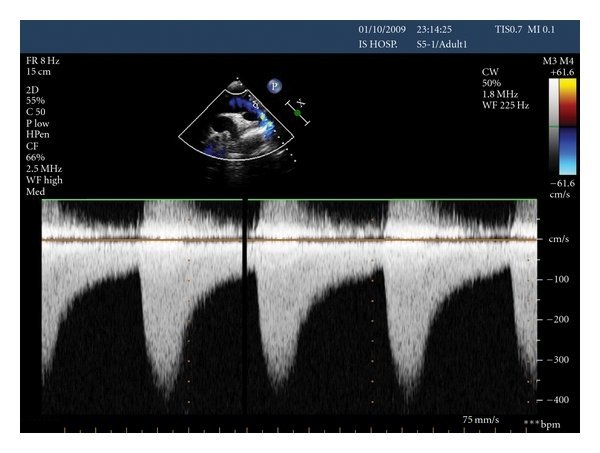

Doppler caracterist of Coarctation of Aorta

A

-Increase Peak Velocity in systole and

-Antegrade flow in Diastoly or pandiastolic foward flow

(so flow that keeps going during sistole)

How well did you know this?